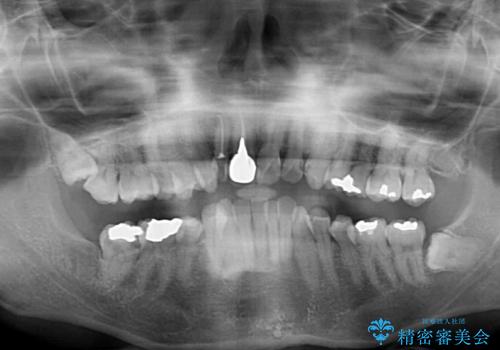

- 前歯の歯並びやむし歯治療の跡、奥歯の銀歯を気にして来院された患者様です。

インビザラインによる矯正治療の後に虫歯や銀歯をセラミックにて補綴することとしました。